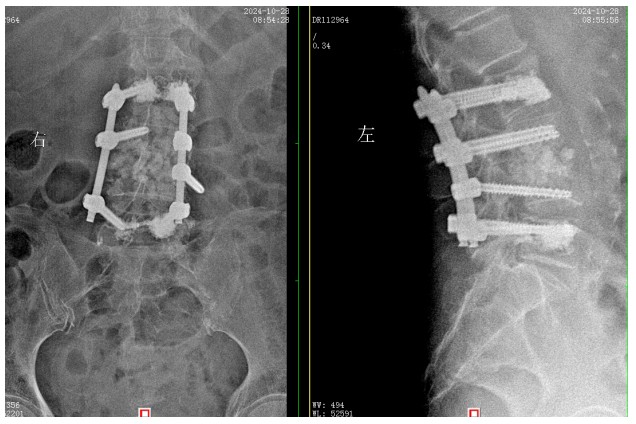

經(jīng)過積極充分的準(zhǔn)備,錢軍博士團(tuán)隊(duì)為患者成功實(shí)施了L3、L4脊柱結(jié)核病灶清除植骨融合內(nèi)固定術(shù),手術(shù)順利,術(shù)后患者腰腿痛癥狀明顯緩解,患者及家屬對治療效果非常滿意,對醫(yī)院的醫(yī)療技術(shù)以及優(yōu)質(zhì)的服務(wù)護(hù)理稱贊不已。